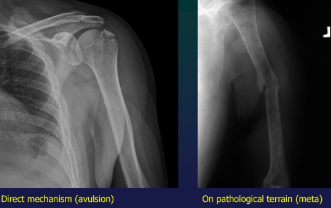

Fractures Classif

Mechanism

direct (direct blow or bone allusion due to ligamental traction)

indirect (bending, torsion, traction, suqatting-crush)

Terrain

commo,, trivial

stress (fatigue)- long term microtrauma

PATHO- on preexisting bone lesion